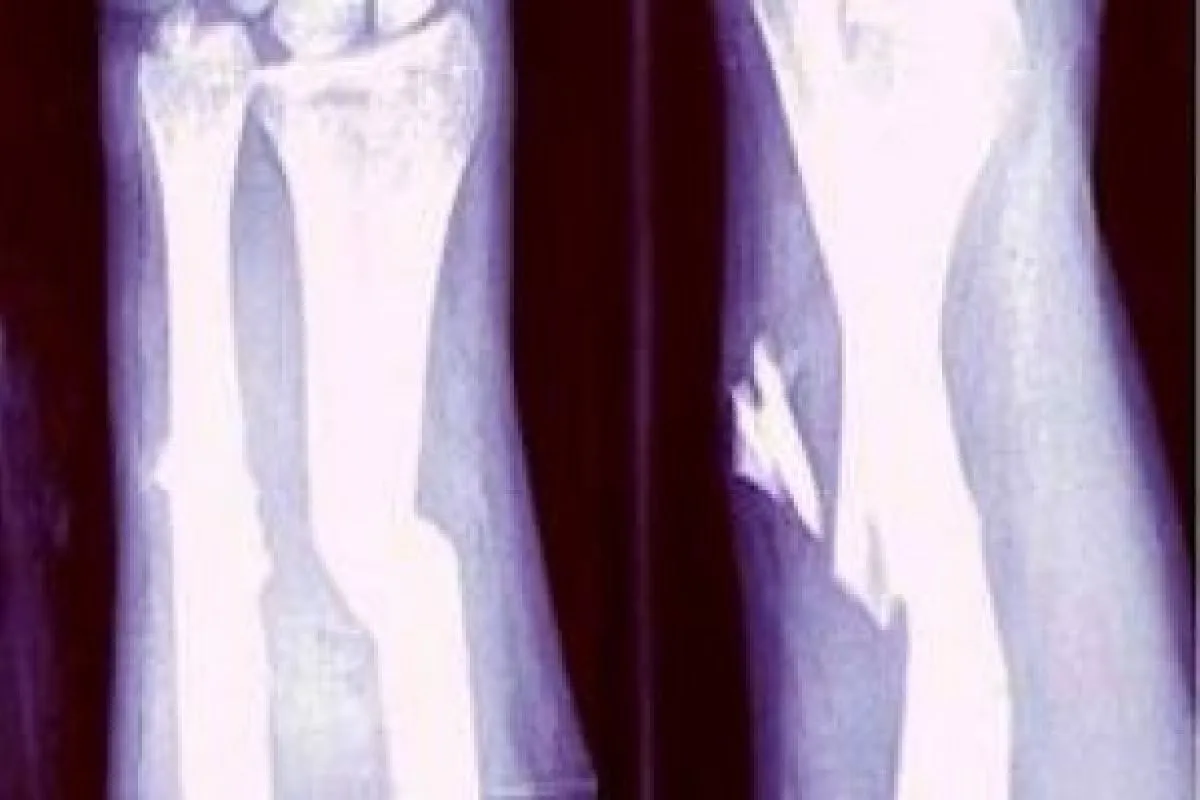

Siswa tersebut, lanjut dia, mengalami kecelakaan dan mengalami luka patah pada sendi telapak kaki sebelah kiri sehingga harus menjalani perawatan.

Orang tua Maula, Iswoyo (48) mengungkapkan, anaknya mengalami kecelakaan pada Jumat (2/5) sekitar pukul 06.30 WIB, di Desa Tanjungrejo, Kecamatan Jekulo.

Selanjutnya, kata dia, anaknya dibawa dan dirawat di tempat pengobatan yang dikenal dengan sebutan sangkal putung Sudirno di Dukuh Pacikaran, Desa Lau, Kecamatan Dawe.